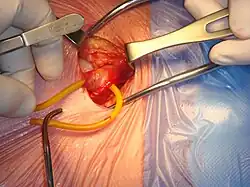

Open surgical repair of a right inguinal hernia | |

Open hernia repair

All techniques involve an approximate 10-cm incision in the groin. Once exposed, the hernia sac is returned to the abdominal cavity or excised and the abdominal wall is very often reinforced with mesh.[11] There are many techniques that do not utilize mesh and have their own situations where they are preferable.[25][17]

Open repairs are classified via whether prosthetic mesh is utilized or whether the patient's own tissue is used to repair the weakness. Prosthetic repairs enable surgeons to repair a hernia without causing undue tension in the surrounding tissues while reinforcing the abdominal wall. Repairs with undue tension have been shown to increase the likelihood that the hernia will recur. Repairs not using prosthetic mesh are preferable options in patients with an above-average risk of infection such as cases where the bowel has become strangulated (blood supply lost due to constriction).[21]